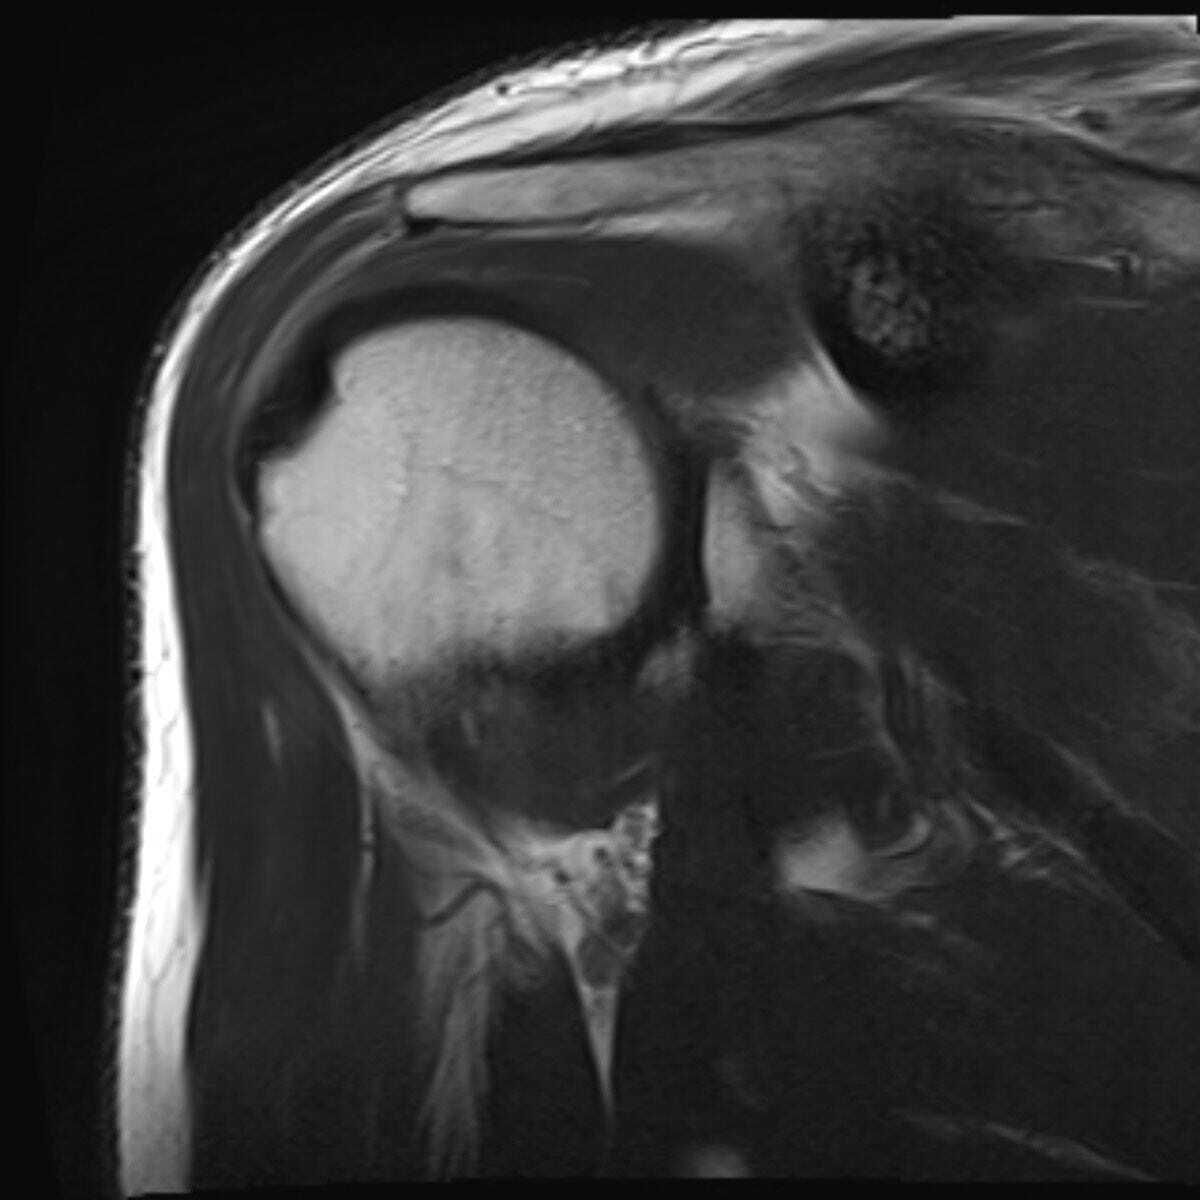

As I advance into middle age and embrace exercise with more enthusiasm than expertise, I’ve given myself a hernia, and a labral tear in one shoulder. More recently I’ve developed incipient arthritis and tendonitis in the other shoulder and one hip. Yet I’ve come to enjoy the penitent, dull repetition of physical therapy stretches and exercises, as well as the semi-brutal joint manipulations of a physical therapist who can bend and reconfigure my body in ways I did not think it could go. But lots of people have it so much worse at my age, for so many reasons, and many never even get far enough to worry about middle age complaints. In this way, minor pains become pleasures of a kind.